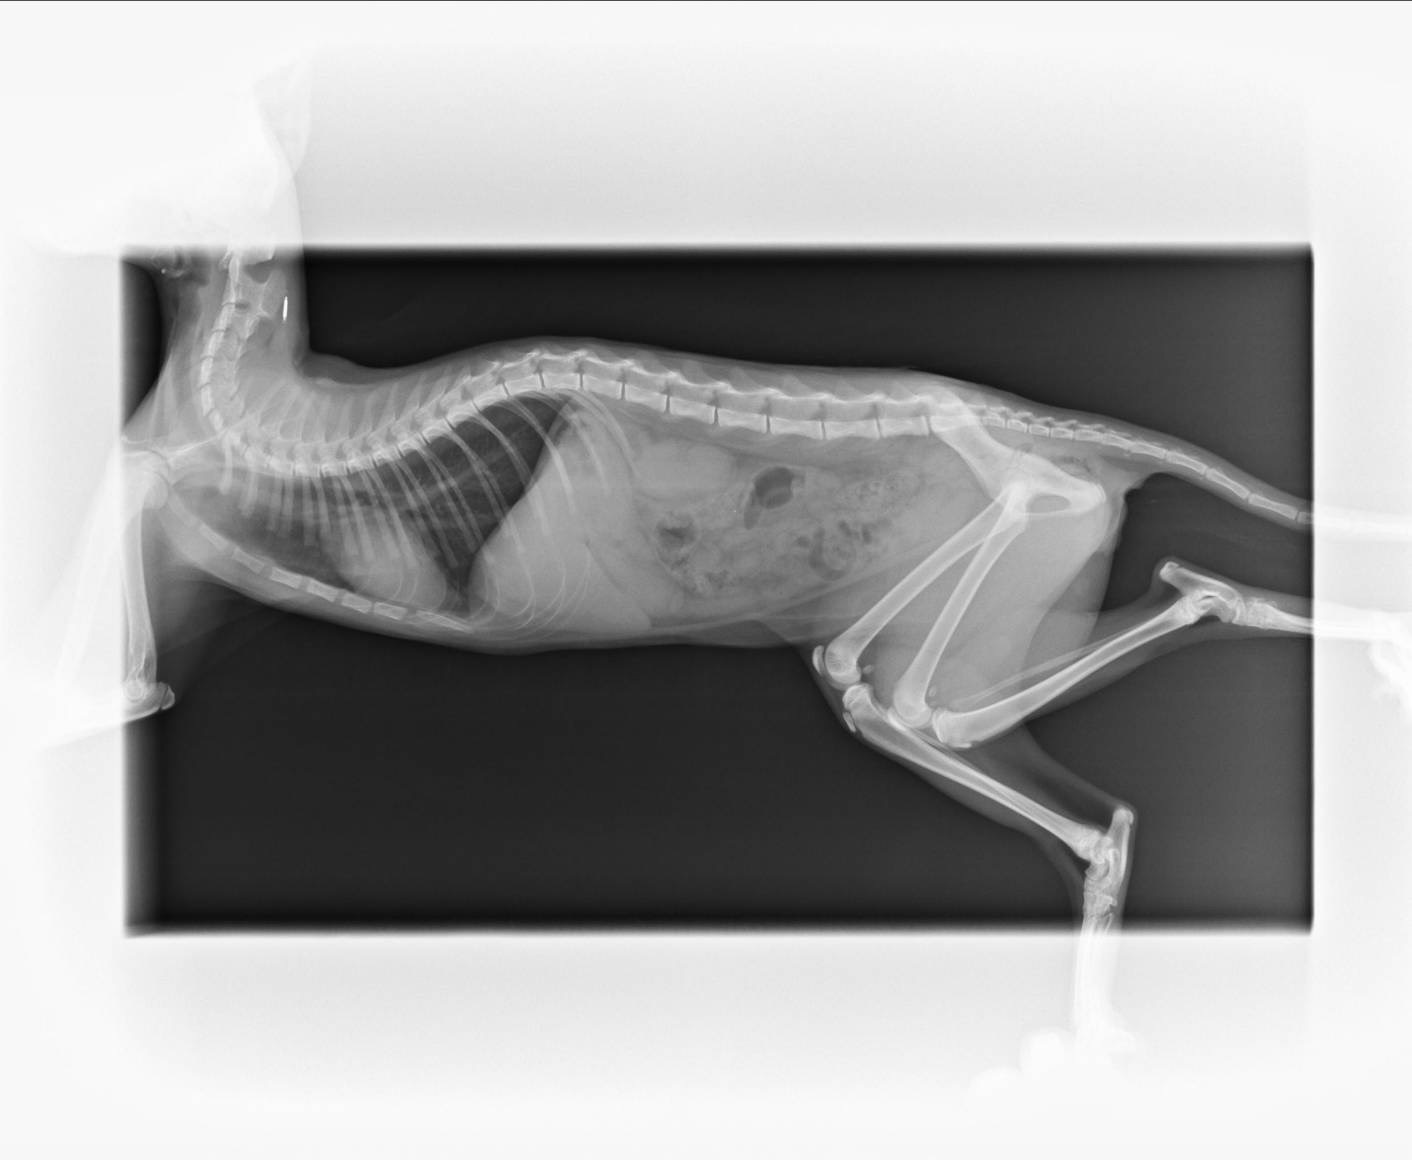

以下為皮皮在不同時間點接受的醫療紀錄、買賣契約書、X光影像、病毒檢驗與血液報告,呈現完整醫療照護歷程與佐證。

▲ X光側面影像,針對腰椎與神經路徑進一步檢查。